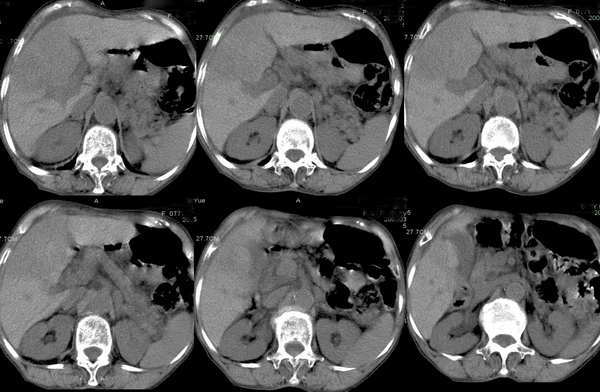

女性,77岁,上腹部不适,下肢浮肿,无其它不良.

今年三月份ct平扫检查.

今天复查ct平扫